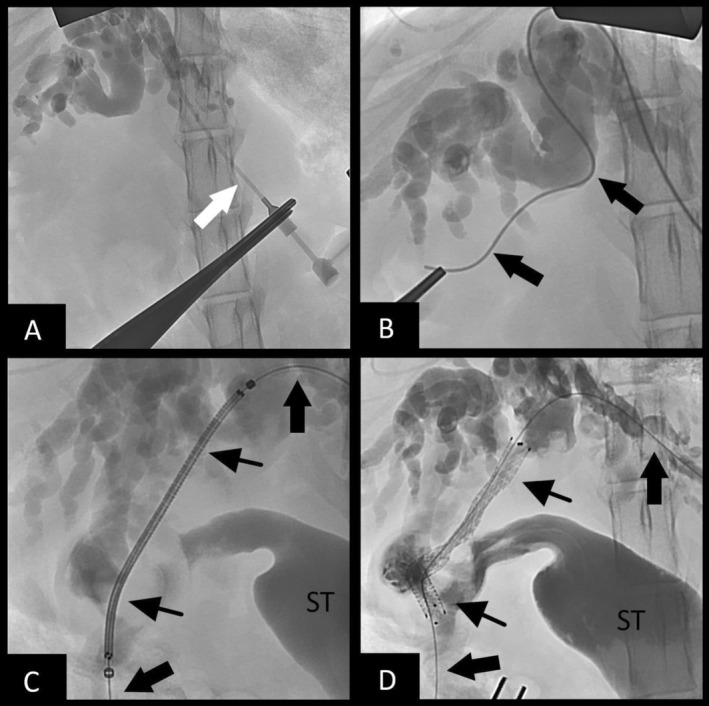

Surgical intervention to pursue biliary stenting was considered. Vitamin K1 (0.6 mg/kg SC) and DDAVP (1.1 mg/kg SC) were given preoperatively. On abdominal exploratory, the tumor was noted to be obstructing the cystic duct, leading to failure of the cholecystoduodenostomy. A rendezvous procedure utilizing a hybrid approach was performed as described above, with some modifications. Biliary access was accomplished through a dilated intrahepatic bile duct of the left lateral lobe. An antegrade cholangiogram confirmed obstruction (Figure 4A). The guidewire and micropuncture system were utilized, as described in case 1, but because of the choleduodenostomy, the wire was passed through the cystic duct, into the gallbladder, and out into the duodenum (Figure 4B). Additionally, instead of retrograde stent placement, a non‐covered SEMS biliary stent (4 mm × 60 mm) was placed in an antegrade manner from the left intrahepatic biliary duct access point, through the cystic duct, and exiting the cholecystoduodenostomy site within the gallbladder (Figure 4C), which was communicating with the duodenum. A post‐stenting cholangiogram confirmed biliary patency (Figure 4D). A locking loop catheter again was advanced over the guidewire and placed into the left biliary duct, and it was left in place connected to a SC access port for potential intraparenchymal chemotherapy. Total procedure time was 111 min. The bile culture was positive for Enterococcus faecium.

Improvement of hyperbilirubinemia and increased liver enzyme activities was noted post‐operatively (Table S1). Post‐operative radiographs showed an appropriately‐placed stent and biliary drainage tube (see Figure 5). A partial kink of the tubing was seen as it entered the body wall, but it was of no clinical consequence. Ultrasonography showed asymmetrical decompression of the intrahepatic biliary duct tracts, with ongoing right biliary obstruction and left‐sided decompression (Figure 6). Echogenic peritoneal effusion and hyperechogenicity of the cranial mesenteric fat also were noted.